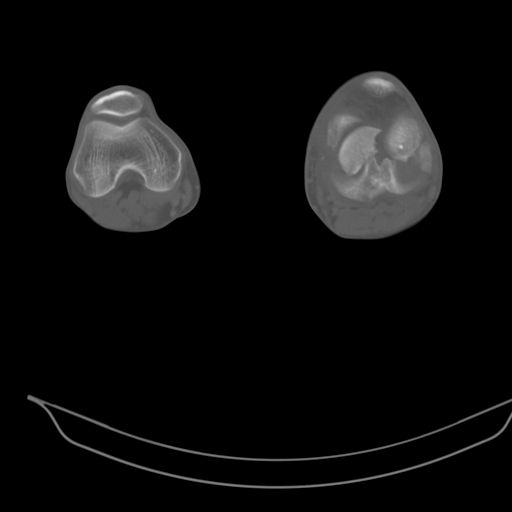

This is a coronal split in the femoral condyle and is a rare injury. Please see attachment for ORIF result

CT shows major bony fragments which are markedly rotated .With this amount of bony damage,you probably should attempt to get reasonably loooking knee with ORIF and thn if he needs a TKR due to pain a few years from now, then tleast you have something looking like a knee that you can replace rather than having to use revision knee for a primary TKR now. 4 weeks is not too long .what is the condition of soft tissues?

При внутрисуcтавных переломах трехмерные (3D) изображения, кроме красивого снимка, не дают полную информацию о состоянии отломков, самыми информативными являются корональные срезы на КТ и обычная длинная ренгенограмма конечности для сравнения оси конечности.

Фронтальные внутрисуставные переломы мыщельков бедра, так называемые Hoffa fracture, не частые, но встречающиеся переломы, в основном они связаны с травмой высокой энергией.

В зависимости от смещения рекомендуется сопоставление костных фрагментов с последующей жесткой фиксацией.

В вашем случае доступ будет медиальный, сопоставить развернутый медиальный мыщелок и фиксацию надо произвести в передне-заднем

направлении шурупами 4.5 мм в диаметре, углубив головку шурупов под хрящ, а поперечную фиксацию - межмыщелковыми шурупами. Желательно применить шурупы 6.3 мм в диаметре. Дополнительная Buttress technique пластина предотвратит перелом от скольжения.

Даже при сросшемся переломе мыщелка рекомендуется реконструктивная операция для предотвращения последующих варус или вальгус деформации.

Место образовавшего костного дефекта после разворота мышелка заполняется спонгиозной аутокостью. Костная пластика применяется даже

в свежем случае.

Под наркозом редрессация, ранняя разработка сустава после операции, нагрузка на конечность через 12 недель помогут удержать без коллапса

фиксацию и поможет больному восстановить функции конечности без артропластики коленного сутава.